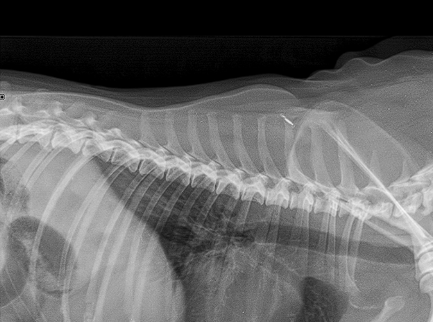

Little area of consolidation but nothing else significant

DX - chronic cough suspicions for airaway disease due to chronic unproductive cough

On left hand side (actually right ariway) airway is compressed

Wouldn’t be ablse to see mass on radiograph as heart borders block ti